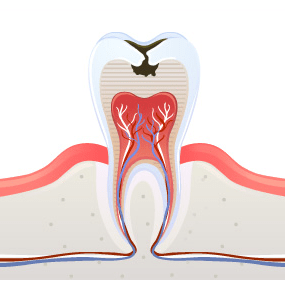

01충치란?

입안에서 서식하는 박테리아에 의해

설탕, 전분 등이 분해해 생기는

산(Acid)이 부식하면서 발생하는 것을

충치라고 합니다.

충치는 증상에 따라 4단계로 나뉘며 방치 시간이 길수록

치료시간과 비용이 증가합니다.

충치가 발생하게 되면 초기에는 통증 등의 이상 증상이 없어

치과에 방문하지 않는 경우가 많습니다.

하지만 충치를 오래 방치할 경우에는 간헐적인 통증이 발생되거나

염증으로 치아가 치아 신경 부위까지 세균에 감염되어 신경치료까지

필요할 수 있습니다. 따라서 정기적인 검진으로 조기에

충치를 발견하고, 필요를 받는 것이 필요합니다.

1 치아표면이 법랑질까지

진행된 경우‘레진 치료’ 가능